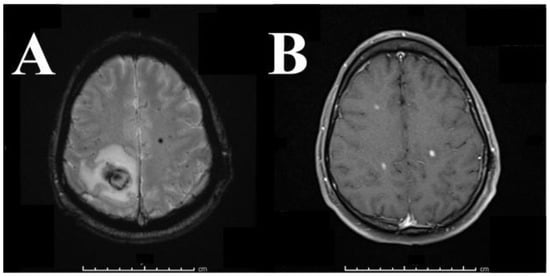

2. Case Presentation